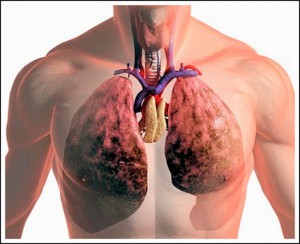

Больной Ц., 28 лет, в течение 4 лет страдал кавернозной формой туберкулеза легких, захватившей все легкое, с наличием крупных каверн в нижнем отделе легкого, трудно доступном для коллапсотерапии. Все виды консервативного лечения, начиная от курорта и кончая массивными дозами стрептомицина и пенициллина, не дали эффекта. Больной продолжал страдать, выделяя туберкулезные палочки в большом количестве, и был нетрудоспособен. Фтизиатры отказались его лечить, и больной приехал из Иркутска специально для операции удаления легкого.

После соответствующей консультации с фтизиатром, тщательного обследования, установившего наличие одностороннего поражения, и соответствующей подготовки больной был подвергнут операции. Под местной анестезией через обычный для нашей клиники разрез была произведена торакотомия в третьем межреберье. Оказалось, что все легкое плотно припаяно к париетальной плевре. Ввиду того, что рентгенологически обнаруживалось большое количество мелких каверн по поверхности, мы, во избежание их вскрытия, вынуждены были убрать целиком вместе с легким всю париетальную плевру. Операция продолжалась 5 часов 15 минут. Послеоперационное течение гладкое. Больной в хорошем состоянии выписался домой. В настоящее время, спустя почти 3 года, он полностью здоров, работает и никаких жалоб не предъявляет. Кашля нет. Анализ на туберкулезные палочки отрицательный.